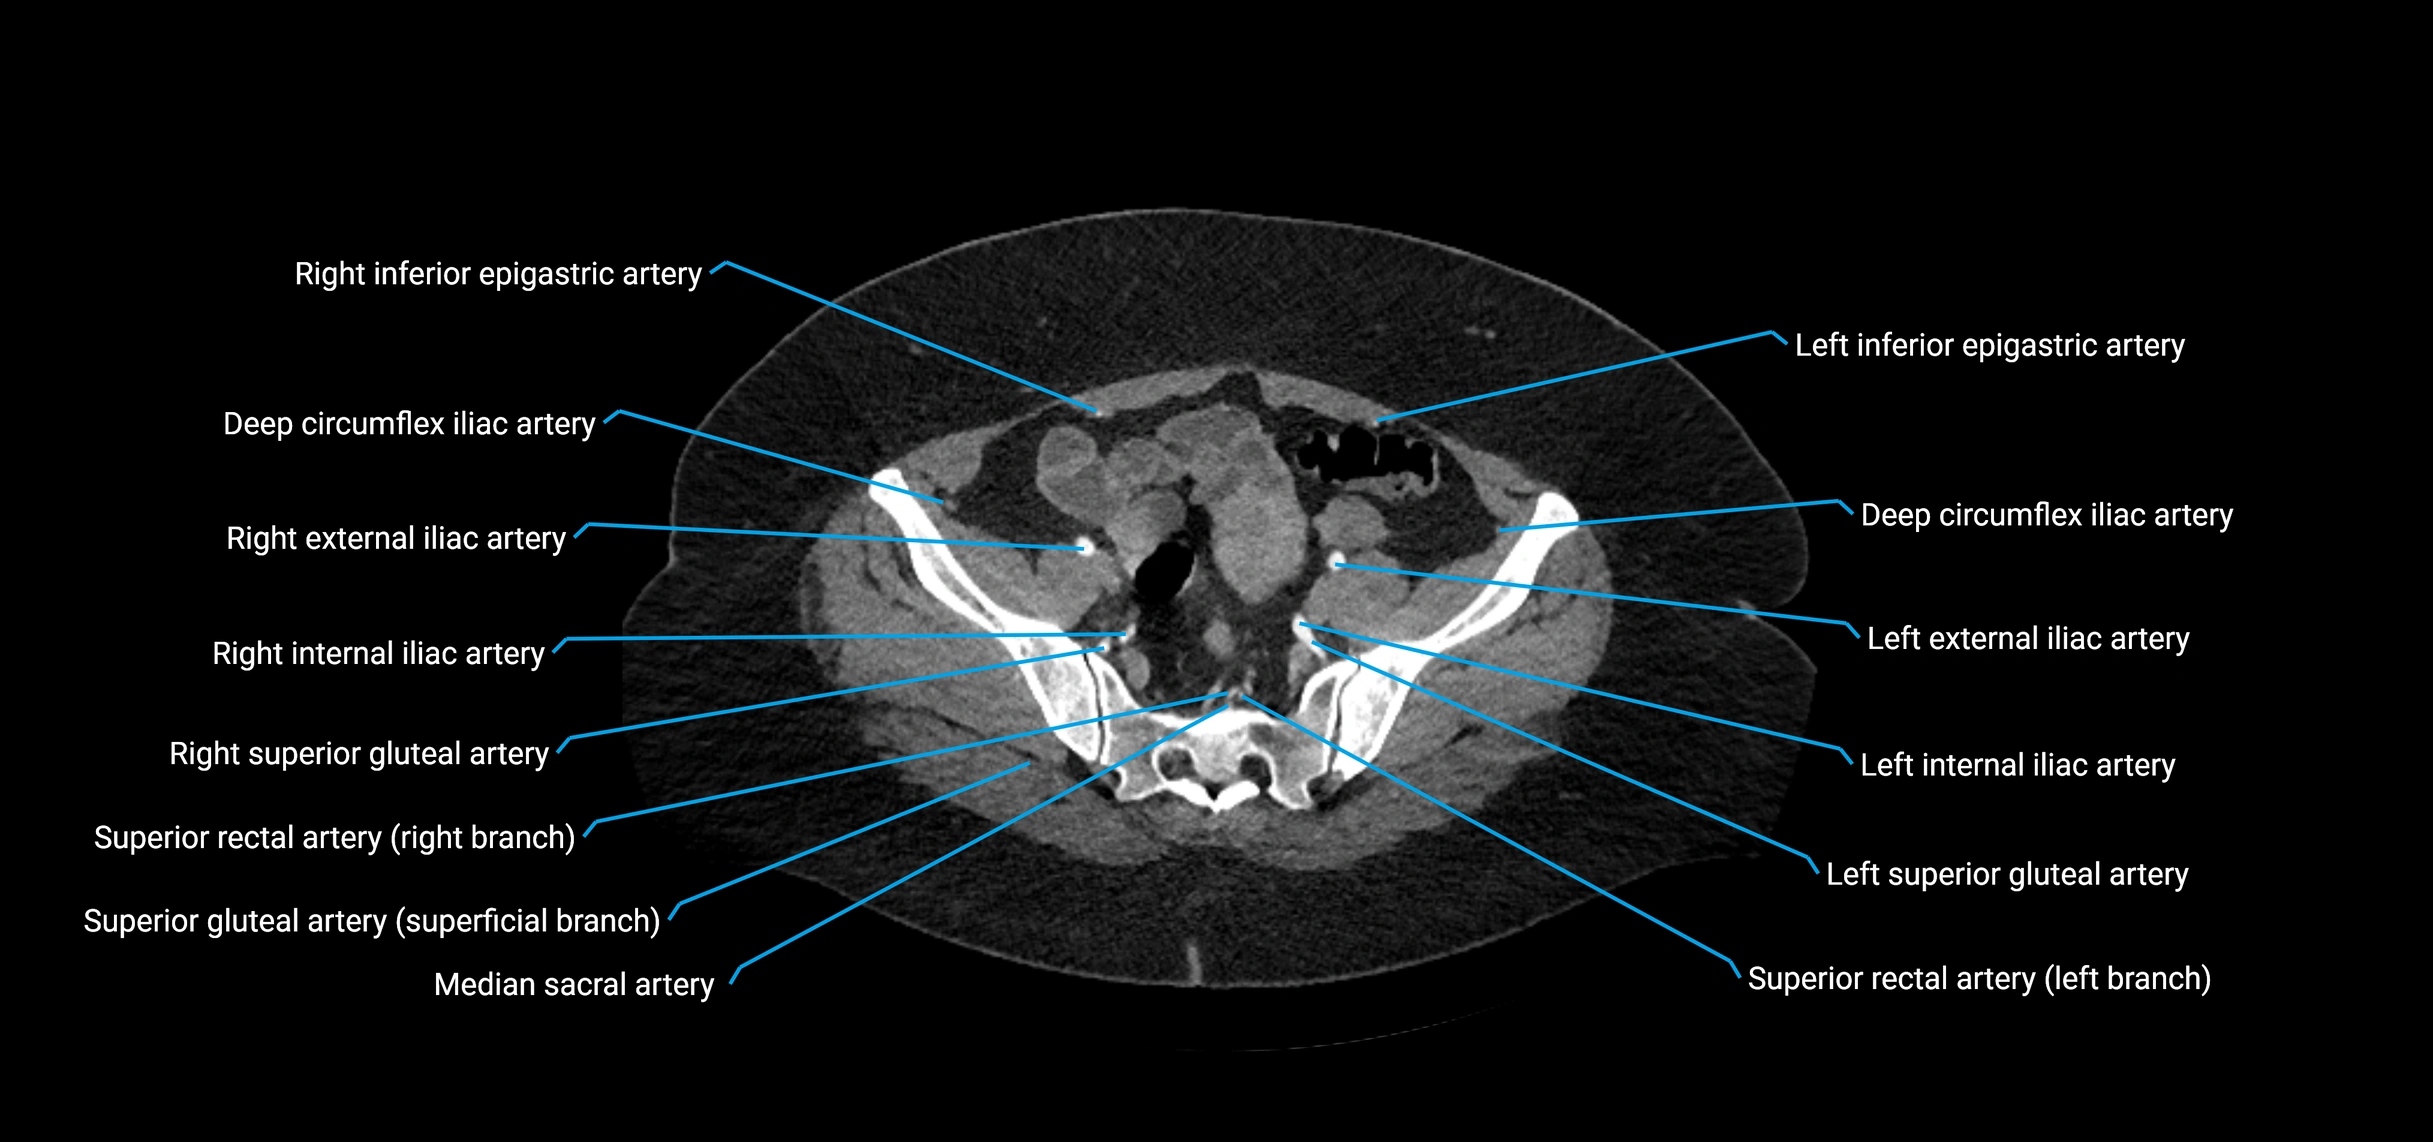

CT images

image

Contrast-enhanced CT (CTA):

• Gold standard for abdominal aortic imaging

• Provides excellent detail of lumen, wall, aneurysm, thrombus, and branch vessels

• Multiplanar and 3D reconstructions help in aneurysm measurement, stent graft planning, and dissection evaluation

• Terminal branches: right and left common iliac arteries